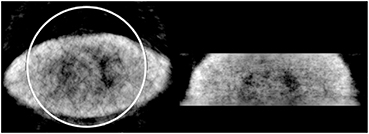

Standard image High-resolution imageFigure 8 shows a larger volunteer of weight of ~ 180 kg that would experience truncation within the CT FOV. This study was performed with arms down and 10 min. The circle illustrates the CT's 50 cm FOV and demonstrates even if this study was performed with arms extended overhead, truncation would still occur to this volunteer. It is observed that the body contour is still resolved and some internal structures are visible such as the lungs and heart, but not as clear as the smaller volunteers' case.

Figure 8. Reconstructed transmission image of large human volunteer. Circle illustrates the CT's FOV.

Download figure:

Standard image High-resolution image3.4. Reconstruction of emission data with Lu-176 attenuation maps